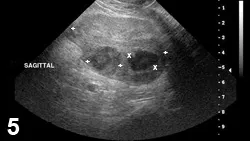

FIGURE 1

Typical ultrasonographic finding with BPH. Transverse image (ventral at top of image) of an intact canine prostate with multiple wagon-wheel striations radiating from the urethra to the capsule.

• Characteristic appearance of BPH and CBPH on ultrasonography includes symmetric parenchymal striation with increased echogenicity and variable hypoechoic-to-anechoic intraparenchymal cystic structures (Figures 1 and 2).